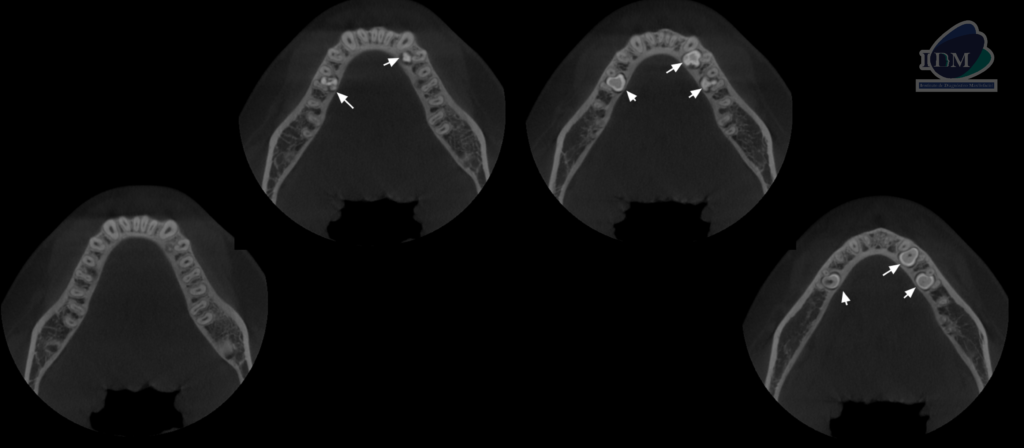

Así mismo en la tomografía volumétrica de haz se evidencia:

CORTES AXIALES